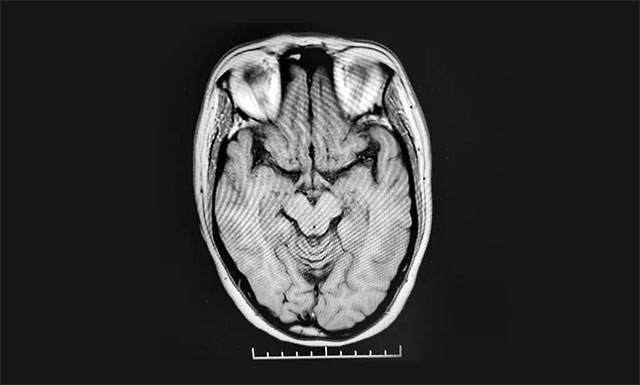

病史资料显示,黔女士近1个月来反复出现头晕、头痛,视物旋转,右侧颜面部痛觉减低,右侧上肢持续性麻木、胀痛、抓握不能,右下肢乏力、行走不稳,左侧肢体感觉异常,并逐渐加重。入院后MR检查显示双侧额叶皮层下微缺血灶。结合病史和影像资料等,黔女士被诊断为脑梗死(脑干梗死),瓦伦贝格综合征。

▲ 患者脑干梗死